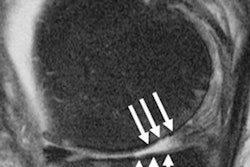

After introducer needle is put into position, the radiofrequency ablation electrode is placed into the introducer needle. Positioning was verified with imaging. All images and caption courtesy of Dr. Felix Gonzalez and the RSNA.After a probe is guided through the introducers, the tip of the probe then imparts radiofrequency to the deep sensory nerves around the knee. Importantly, the water circulating through the system enables greater dissipation of heat from the probe's tip, according to the researchers.

Cooled radiofrequency ablation technique.The authors note that the long-term relief from cooled RF ablation is a major advantage over cortisone injections, which only provide an average of about three months of pain relief in treating knee arthritis. The procedure can be easily repeated as it's minimally invasive, and it can also reduce or eliminate the use of opioid pain relievers.